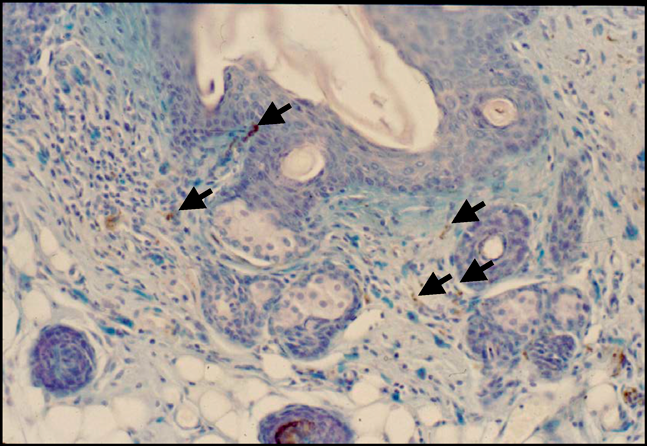

図3 皮膚病変のマスト細胞

12週齢のconventionalマウスから採取した皮膚を顆粒内に含まれるヘパリンに特異的に結合するtoluidine blueで染色すると異染性のマスト細胞の多くは脱顆粒しており(矢印),活性化状態にあることが判明した(上部).そして,抗IgE抗体で免疫染色するとAlcian blue染色陽性のマスト細胞が陽性反応を示した(下部,矢印).